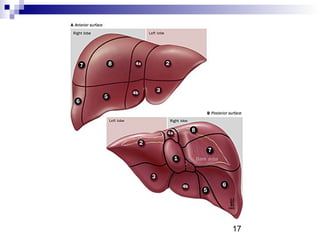

17

Sektörler Segmentler